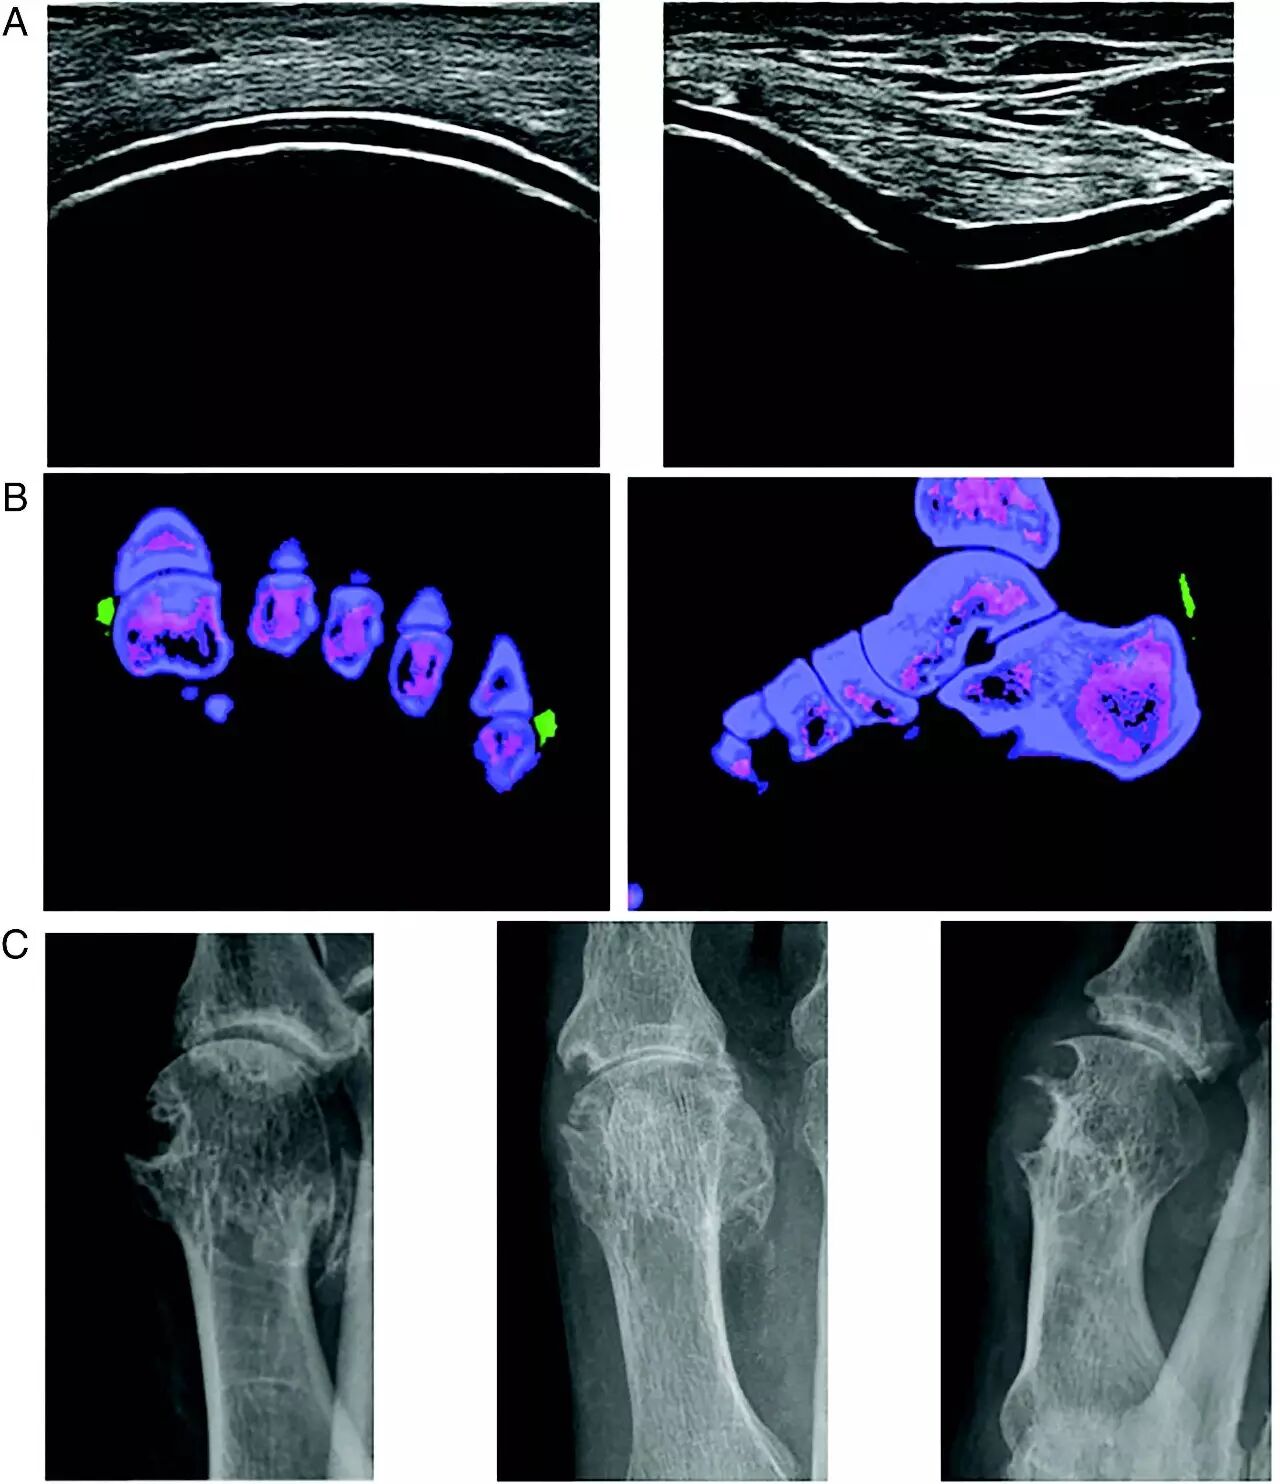

图2 痛风影像表现

(A)超声双轨征,左图为股骨关节软骨纵向超声图像;右图为股骨关节软骨横向超声图像。图示无回声的软骨表面覆盖高回声的条带——MSU晶体在关节软骨表面沉积,其特异性95%~100%,敏感性21%~92%。

(B)双能CT,左图为尿酸盐沉积于第1和第5跖趾关节;右图为尿酸盐沉积于跟腱处。

(C)骨侵蚀,第1跖趾关节X线片表现。